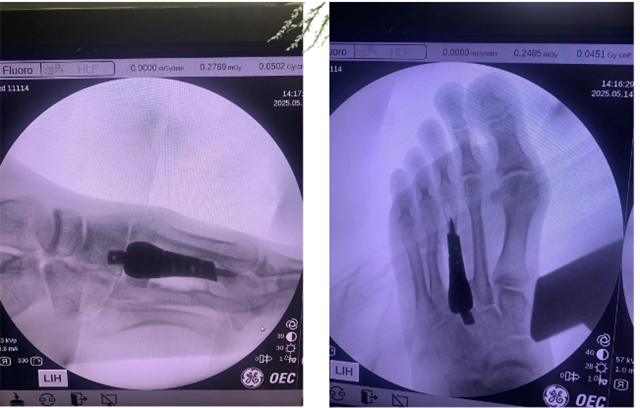

经一周精密筹备(CT扫描→三维建模→假体打印),徐杨博团队实施微创植入术。术中见假体与残端完美契合,术后影像显示力学轴线精准复原。